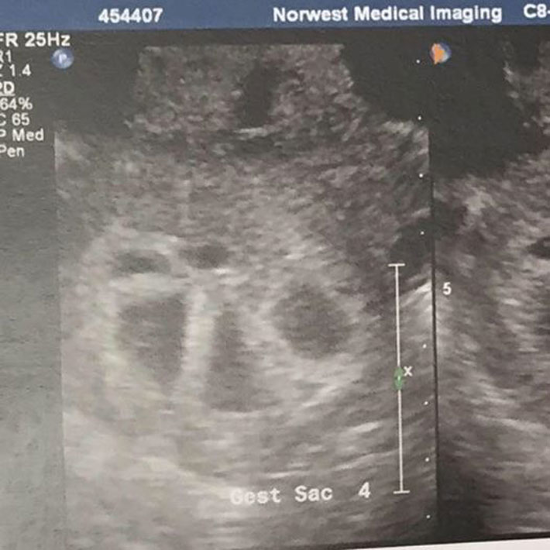

在她的第一次超聲波檢查的時候,醫生超驚訝地數著,「一個、兩個、三個、四個、五個!!!」Tucci以為自己聽錯了,但醫生非常確定地告訴她,就是五胞胎。

這張照片拍於懷孕第11週。Tucci說:「我懷疑自己是雙胞胎,但我萬萬沒想到,竟然是五胞胎!」